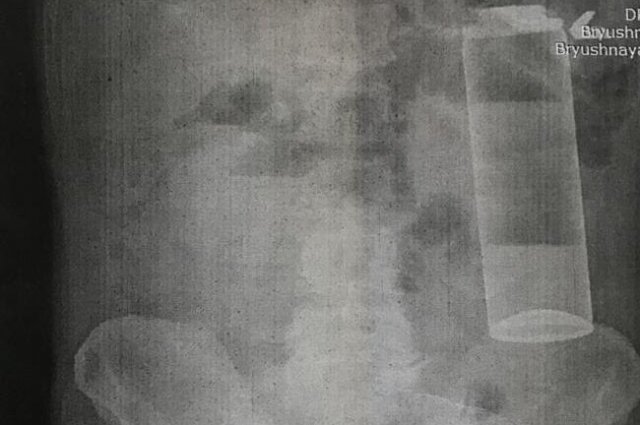

Пациент с баллончиком Фото: Из архива героя публикации

«Подобные действия крайне опасны, ведь предметы не имеют ограничителя, поэтому легко соскакивают, сфинктер сокращается и предмет уходит вверх, в так называемую ампулу прямой кишки. Самостоятельно достать оттуда их уже невозможно, можно почувствовать только кончик. Список различных предметов цилиндрической формы, которые мы извлекали из пациентов, обширен», – сказал проктолог.